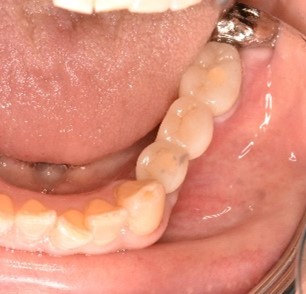

女性Kさん 70代(インプラント)

左下、ブリッジの支台になっていた奥のほうを抜歯したままになっている。ここのところを何とかしたい。

治療内容

ブリッジの奥に伸びていた部分を削り取り、インプラントを2本入れました。

所感

左下ブリッジのところを切り離し、奥を抜歯したままになっていました。このままでは、ブリッジの前方の支台になっていた歯に負担がかかり、将来抜歯になる可能性があることをお話ししました。歯がないところを補う方法には、部分入れ歯かインプラントがあることを説明すると、自分の歯と同じ感覚で食事ができるインプラントを選択されました。X-Guideを使用し埋入しました。口を大きく開けることができない方でしたので、X-Guideの長所のうちの一つを活かすことができました。

インプラント2本:¥363,000×2本=¥726,000(税込)

Before

青丸の部分を削り取りました

After